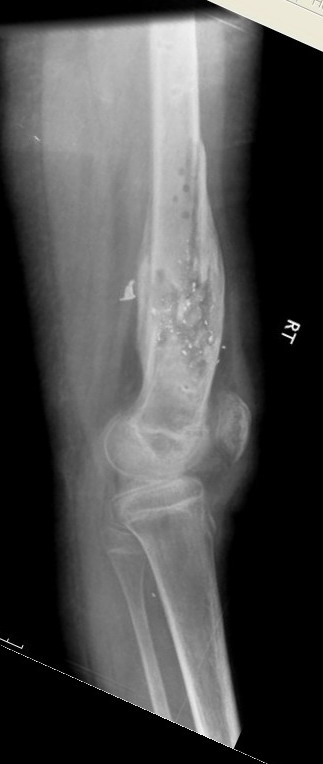

Выше приведены рентгенограммы 13-летнего подростка, страдающего от огнестрельного многооскольчатого перелома дистальной трети бедра. AO наружный фиксатор наложенный в день травмы не дал приемлемой редукции. Через три недели после перелома аппарат Илизарова был наложен без попытки одномоментной репозиции на операционном столе. There are X-Rays of a thirteen year old boy with a comminuted distal femur fracture secondary to a gunshot wound, initially treated with an AO external fixator. The alignment was unacceptable and an Ilizarov external fixator was applied three weeks after the injury. No attempt of definitive reduction was made during the surgery.

Гексаподная приставки наложена на 10 дней и приемлемая редукция была получена. The Hexapod set was applied for ten days and acceptable reduction was received.

По окончанию редукции Гексаподный сет был снят и дальнейшее ведение больного проходило в стандартном режиме аппарата Илизарова. Хороший анатомо-функциональный результат был получен. When reduction was finished, the Hexapod set was removed and further management has been continued by standard Ilizarov regime. Good anatomic and functional results were achieved.